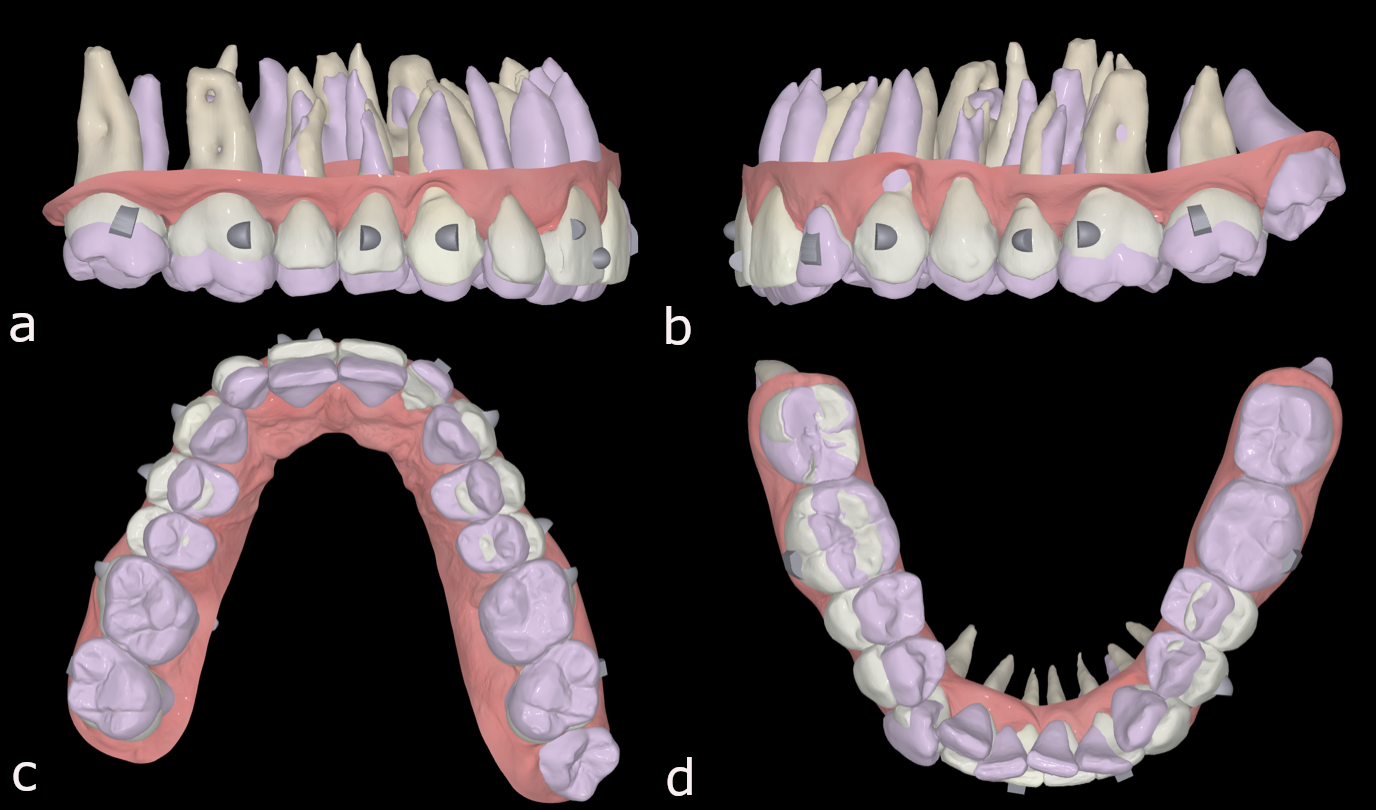

Figs. 45a–d: Pretreatment situation (purple) and expected post-treatment situation (white) in FAS OcclusalDesign.

The treatment plan with FAS consisted of aligning and levelling both arches, recovering arch forms and introducing positive torque to the entire maxillary arch, intruding the maxillary posterior teeth with the help of skeletal anchorage (vertical control) to correct the Class II malocclusion and opening space for the lateral incisors for their restoration (Figs. 45 & 46).